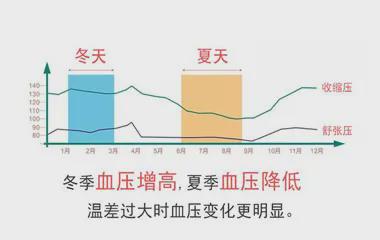

血管反应: 低温促使血管收缩,阻力增大,血压升高;高温导致血管舒张,阻力减小,血压趋向降低。

量化关系: 研究表明,气温每降1°C,收缩压平均升1.14 mmHg,舒张压升0.58 mmHg。故夏季平均血压常比冬季低 6-12 mmHg。

幅度差异: 敏感人群(如老年人、糖尿病患者、自主神经功能异常者)波动可达 30-40 mmHg,远高于常人(5-10 mmHg)。

类型差异: 老年人收缩压波动更显著;年轻人舒张压变化可能更明显。